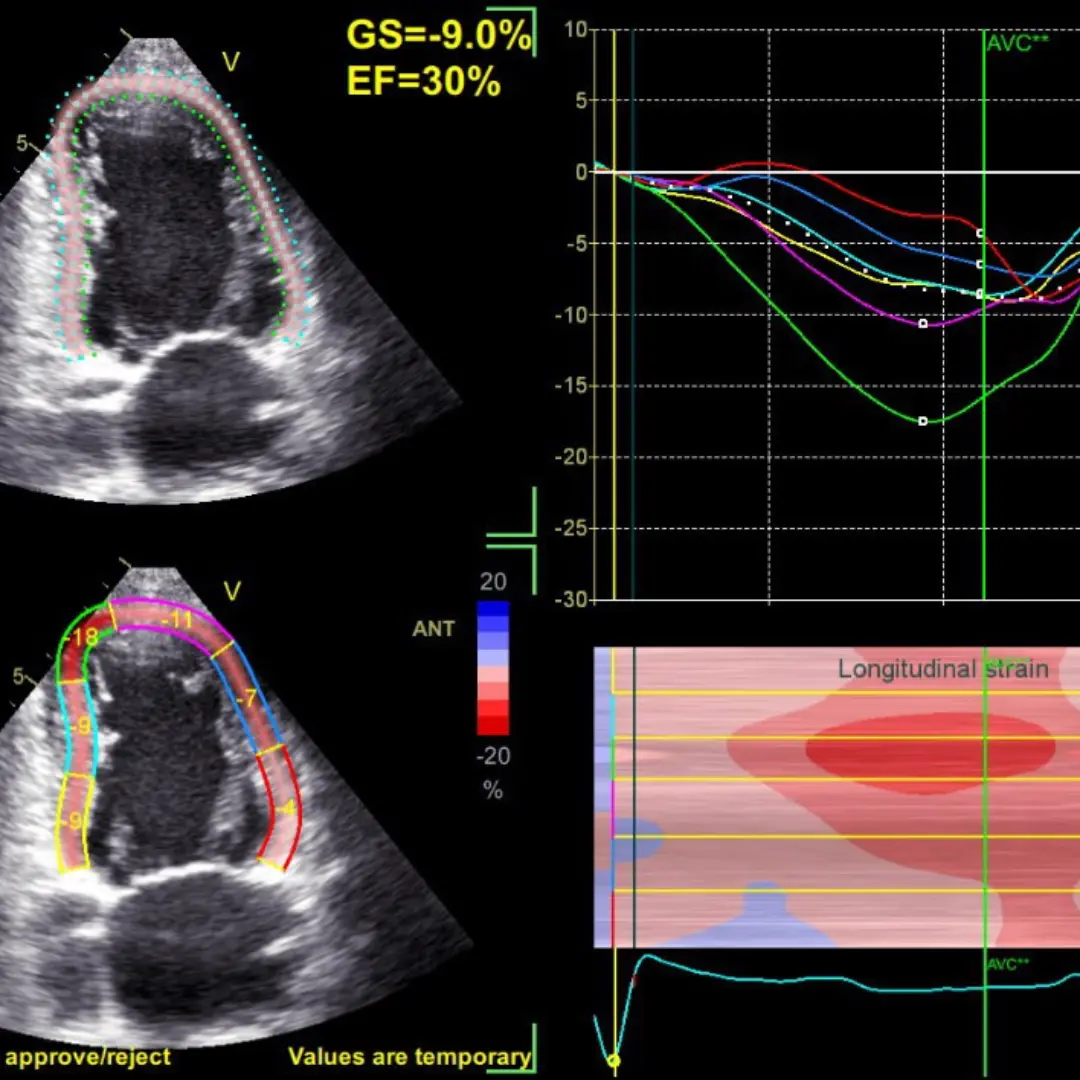

Стрейн ЕхоКГ (спрекл-трекінг) – це сучасна діагностична методика, яка доповнює та розширює можливості звичайного УЗД серця (ЕхоКГ) та дозволяє краще оцінити скоротливість міокарда, тобто ефективність роботи серця як насосу.